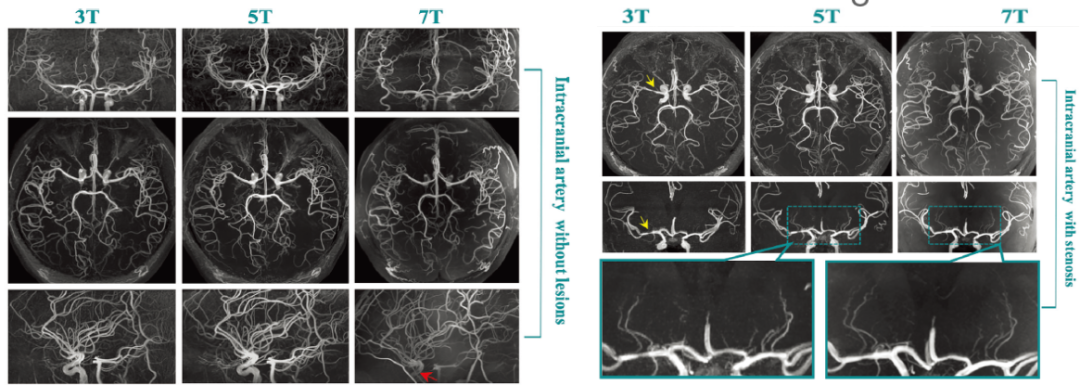

2022年,曾蒙苏教授团队与复旦大学张江国际脑影像中心合作的基于联影医疗5T磁共振最新研究成果登上国际顶级放射学期刊《Radiology》(if=29.014) ,该研究发现5T脑动脉TOF-MRA在图像质量和脑动脉远端分支及侧支小动脉的呈现上与7T效果近平相当,而显著优于常规3T成像。

代表性TOF-MRA图像。注:7-T MRI 扫描显示颈动脉虹吸管中的信号强度损失(红色箭头)。 在左侧大脑中动脉的狭窄部位(黄色箭头),5-T 图像上的豆纹动脉和 7 T 图像上的豆纹动脉均可见。